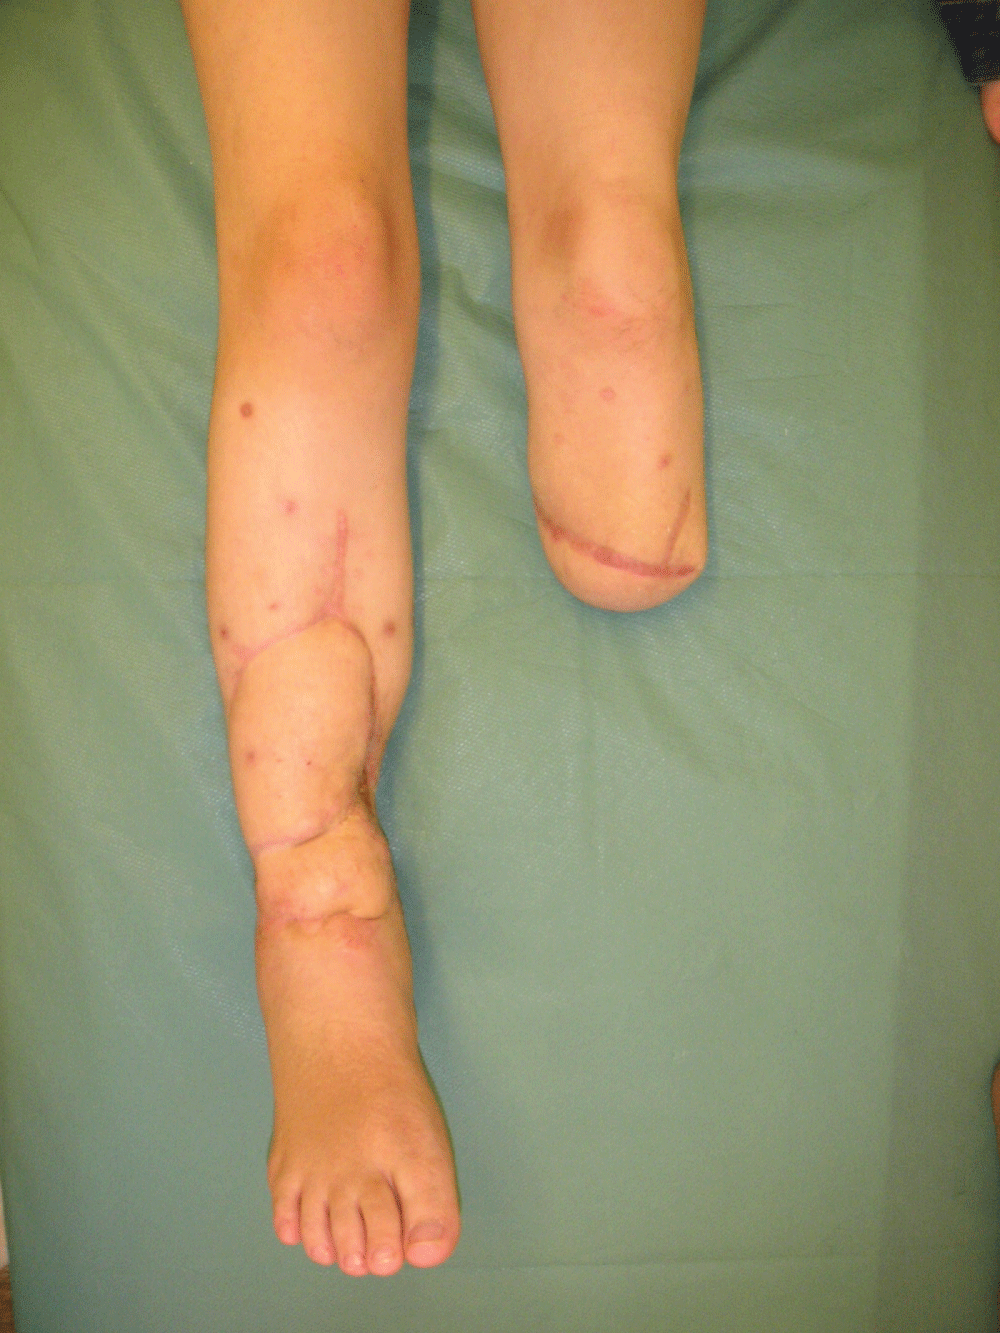

Complete healing of primarily infected complex segmental tissue defect on right tibia and sound healing of below knee stump on the left side was achieved. The patient was able to walk using PTB prosthesis with no visible limp (Figure 8, Figure 9). The ankle joint was stable with ROM of 0 degrees dorsiflexion and 45 degrees plantarflexion with no sensory deficit in the foot. The growth plates were not damaged during the procedure and no growth disturbances were observed, still, the comparison with the contralateral shin was not possible No recurrence of infection was observed within 10 years after the surgery (Figure 10).

The discussed case demonstrates that: a crossover pedicled composite tissue transfer from one leg planned for amputation on selected level can salvage the opposite leg in case of high-grade bilateral open fracture of distal part of lower extremity resulting in segmental osteomyelitis of one tibia.